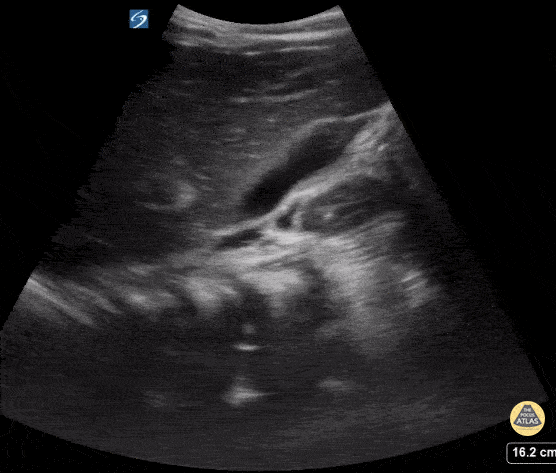

16 yo with abdominal pain. Normal gallbladder in long axis. Contributor: Kathryn Pade, MD, Rady Children's Hospital San Diego